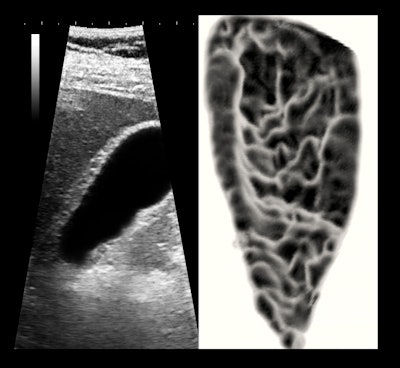

If I were to do something similar today and be limited to a midperformance unit, I would add inspection of the anterior wall for chronic focal cholecystitis, since this finding seems to precede stone formation by several years. I would also rely on 3D surface rendering of the lumen, because even a half-second scanning of 16 frames will improve the signal-to-noise ratio by 400% over a single-frame image (see below).